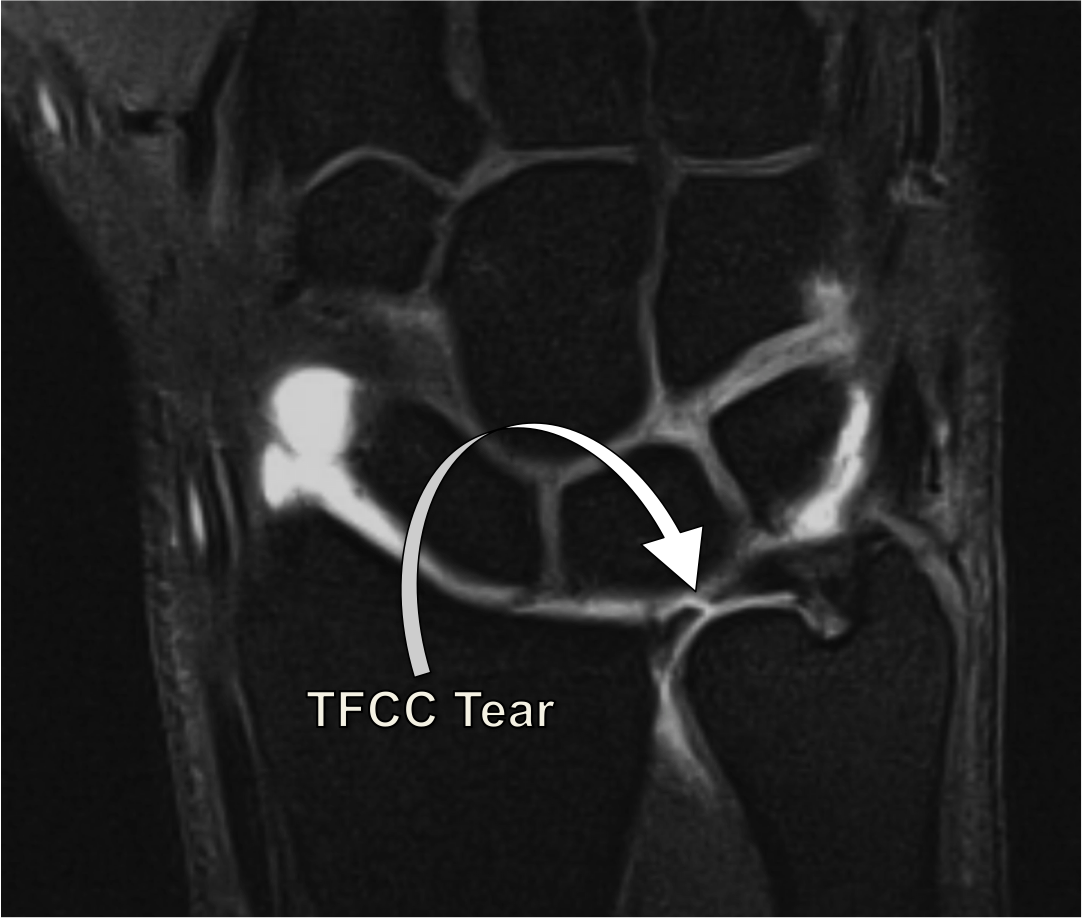

Daily Dose: TFCC tear.

Check out my new book: Working as a radiology consultant, reporting msk studies every day, i have gathered a comprehensive knowledge, which i know would like to share with a wider audience. The ability to perform complex movements is of uppermost importance for hand function. Head and lunate, deg perforation of disc, tear of lunotriquetral lig. The tfcc is located on the ulnar aspect of the wrist joint between the ulna and the lunate and triquetrum of the proximal carpal row. The tfcc is a complex structure consisting of the triangular fibrocartilage (tfc) disc proper, ulnomeniscal homologue and numerous ligaments and tendons. Although all of the components of the tfcc are structurally important, from a radiologic and an orthopaedic perspective, it is the articular disc and the radioulnar ligaments that. 1department of imaging and interventional radiology, prince of wales hospital, the chinese university of hong kong, hong kong, china the purpose of this article is to review the anatomy of tfcc, state of art mri imaging technique, normal appearance and features of tear on mri according. Direct mr arthrography is especially useful for evaluating tfcc as well as wrist ligaments (fig. The tfc demonstrates low signal intensity on all sequences and a hobby jl, dixon ak, bearcroft pw, et al. Central perforation of the triangular fibrocartilage (tfc) disc proper b: Tfcc components triangular fibrous cartilage complex (tfcc) components triangular fibrous cartilage / articular disc dorsal & volar radioulnar ligaments ulnocarpal ligaments ( ulnolunate , ulnotriquetral. A tfcc injury typical presents with ulnar sided wrist pain and can result in a distal radioulnar joint (druj) injury.